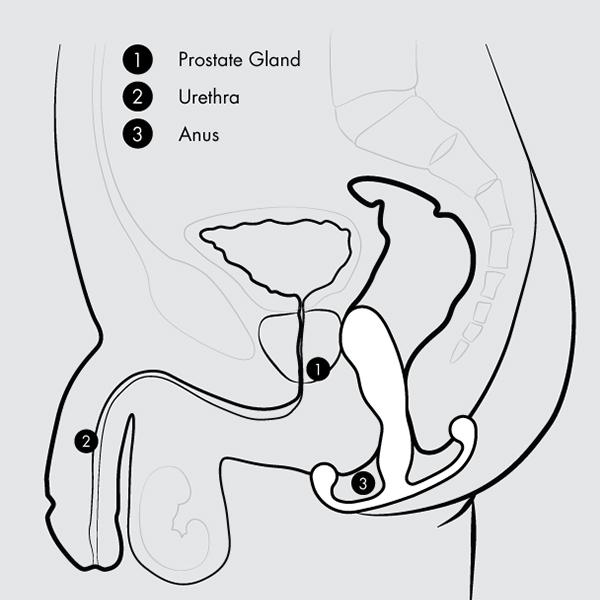

De Aneros Eupho Trident is het meest verfijnde lid van de Trident-familie. Met zijn slanke body en elegante rondingen is deze prostaatstimulator ontworpen voor precisie en subtiele diepte. Perfect voor ervaren gebruikers die verlangen naar een intens maar verfijnd spel met hun P-spot.

Dankzij de revolutionaire Multi-Axial Motion Architecture (MAMA) beweegt de Eupho Trident vrij in meerdere richtingen: zijwaarts, op en neer én roterend. Elke contractie van je bekkenbodemspieren zet de stimulator in beweging, waardoor een golf van sensaties ontstaat die je prostaat en anale kanaal verfijnd masseren.

Tijdens geslachtsgemeenschap komt de Eupho Trident pas écht tot leven: de slanke body beweegt vrij mee met de stoten van je partner, waardoor je orgasmes dieper, krachtiger en langer worden. De gebogen kop raakt je prostaat direct, terwijl de perineum-tab en de Kundalini-tab externe stimulatie toevoegen – samen goed voor een orkest van prikkels dat je hele lichaam laat meetrillen.